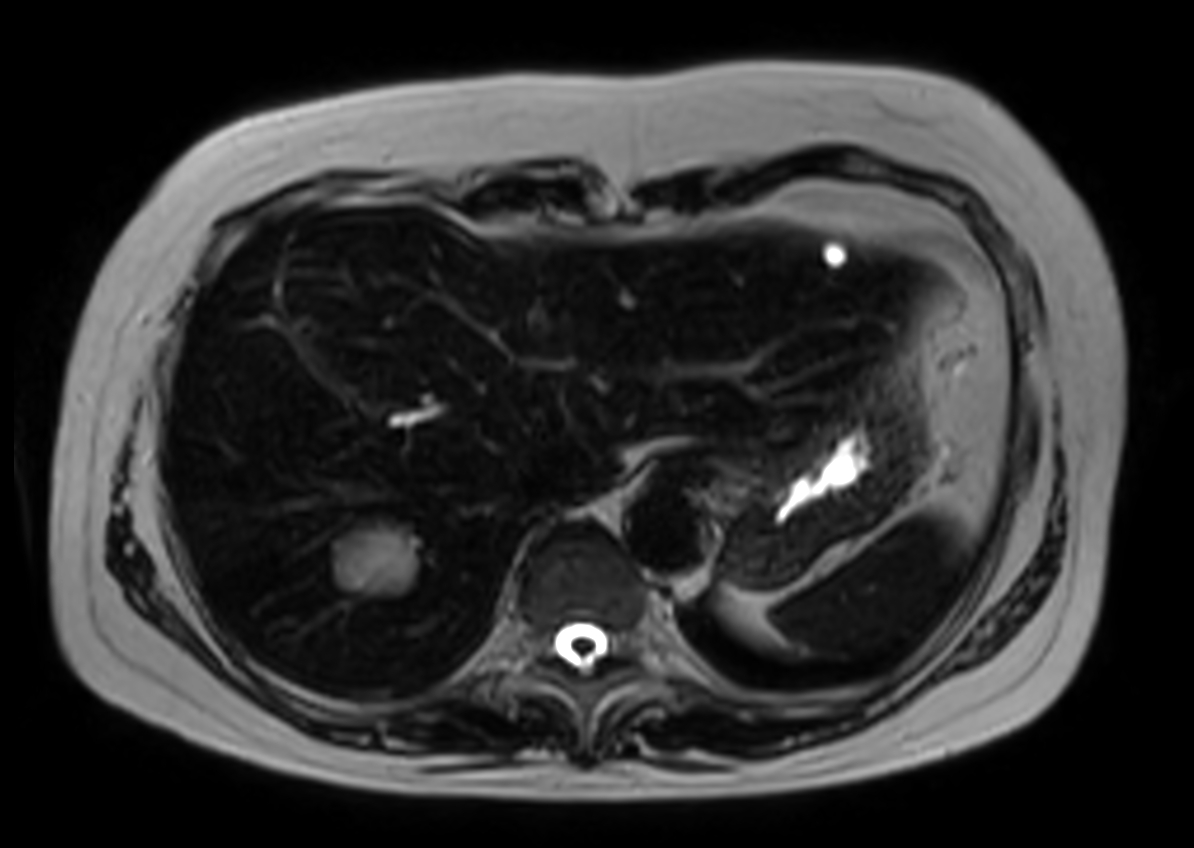

Axial mDIXON XD FFE (In Phase)